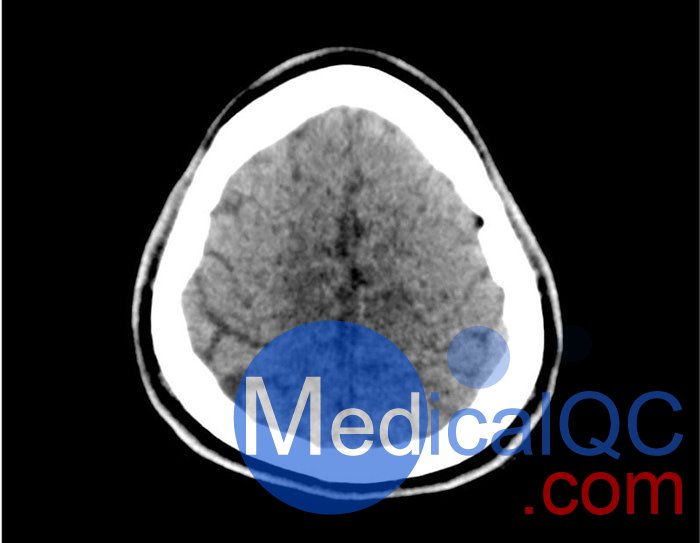

50-01頭部CT模體,50-01腦中風(fēng)頭部模體,50-01腦出血頭部模體模擬了具有中風(fēng)和出血模式的頭部。它覆蓋枕骨大孔的頂點(diǎn)。

出血模式包括蛛網(wǎng)膜下腔出血、不同年齡的硬膜下出血、腦室內(nèi)出血和腦出血。

出血

• 蛛網(wǎng)膜下腔出血(2個(gè)地區(qū))

• 不同年齡的硬膜下出血(3個(gè)地區(qū))

• 腦室內(nèi)出血(左側(cè)腦室)

• 腦出血(2 個(gè)丘腦,6 個(gè)皮質(zhì)下)

50-01頭部CT模體,50-01腦中風(fēng)頭部模體,50-01腦出血頭部模體影像效果圖: